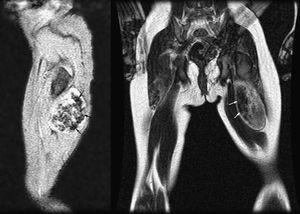

En la RM la masa está contenida en el bíceps crural izquierdo, sin afectación ósea asociada (Figura 2). Internamente se apreciaban áreas irregulares de vacío de señal (Figura 3) (hipointensas en todas las secuencias), secundarias a la presencia de calcificaciones (flechas).

Figura 3.